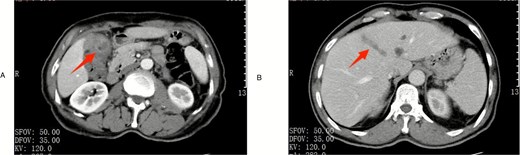

A 63-year-old male presented for elective right inguinal hernia repair. Preoperative laboratory tests were unremarkable except for elevated C-reactive protein (11.4 mg/L). Abdominal computed tomography (CT) incidentally demonstrated gallstones, significant gallbladder wall thickening (Fig. 1A), pericholecystic stranding, and a filling defect in the middle hepatic vein suggestive of thrombosis (Fig. 1B). Tumor markers (Alpha-fetoprotein [AFP], CA19-9) were within normal limits.

Preoperative imaging. (A) Contrast-enhanced CT scan in the arterial phase demonstrating gallbladder wall thickening with enhancement (arrow). (B) Contrast-enhanced CT in the venous phase showing thrombus formation within the middle hepatic vein (arrowhead).